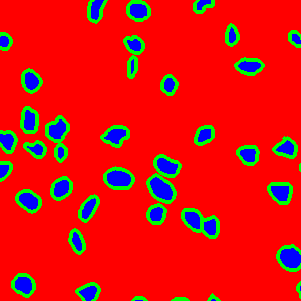

The task of nuclei segmentation can be roughly divided into two stages: the first stage is extracting the foreground(nuclei), the second stage is segmenting the connected foreground area into separated nuclei and finding out the boundary of each nucleus. Our method intends to merge these two steps by extracting the nuclei and their edges at the same time. That is the reason why it is named ”nuclei-boundary(NB) model”. As shown in Fig.3, the output of the NB model has three channels, each has the same height and width with the input image. Its values represent the probabilities of each pixel being , or class, respectively. The manual annotation for our segmentation problem is the boundary of each nucleus. A pixel belonging to the class means that it is on or inside an annotated boundary and within 2 pixel from the boundary. Pixels of the class are those that are inside annotated boundary but are not pixels. Correspondingly, the output can be regarded as an RGB image and the estimated maps of the , and are represented by red, green and blue, respectively, as shown in Fig.3. To generate the ternary mask for training, we apply a morphology operator to each nucleus to obtain the pixels, and then subtract pixels from the nucleus to get pixels.

Figure 6 shows how our method segments the nuclei step by step. The color variety is well controlled by the color normalization procedure. The prediction result shows clear nuclear areas and nucleus boundaries. In the final segmentation result and ground truth image, each nucleus is represented by a different color.